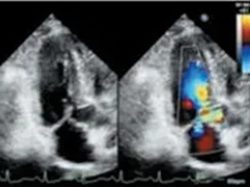

目标导向Valsalva 设备

目标导向Valsalva 操作过程